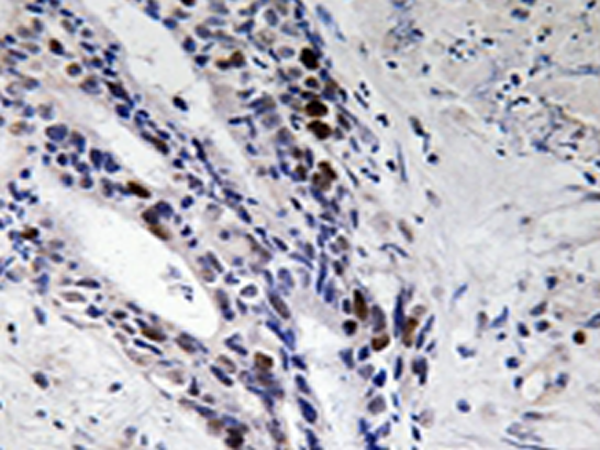

IHC positive control: |

Human colon carcinoma tissue |